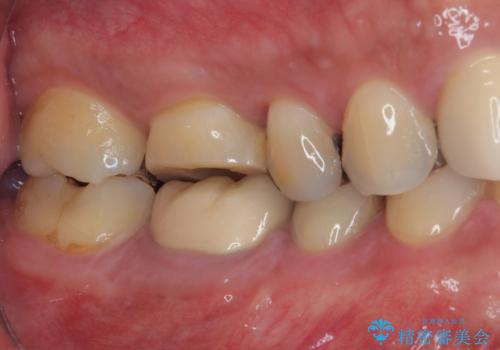

治療途中の奥歯 オールセラミッククラウンでのむし歯治療

- 近医にて治療を行っていたものの、痛みがなかなか引かないとのことで転院されてきた患者様です。

上下で接触しないように削られていたため、日常生活で痛みを感じることはありませんでしたが、歯を叩くと痛みを感じる状態でした。

前医ではラバーダムの装着をされていない状態で根管治療を行っていたようで、その他の器具や処置も無菌的環境下であったとは考えにくいため、それが痛みがなかなか引かない原因の一つであると考えられました。

根管治療後に痛みの消失を確認し、オールセラミッククラウンにて補綴治療を行うこととしました。